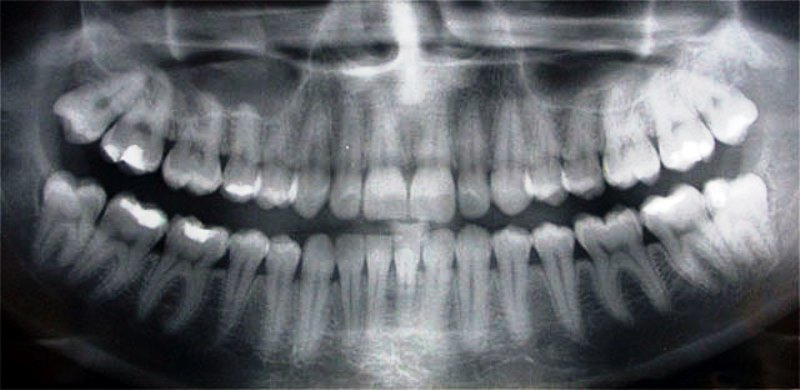

Панорамный рентген, или «Панорекс», как его сначала назвали, — замечательное современное изобретение. Он имеет гораздо меньше радиации, чем традиционный полный набор из восемнадцати (18) рентгеновских снимков меньшего размера, и пациенту гораздо удобнее его делать. Панорамный рентгеновский снимок также можно сделать очень быстро, и он особенно полезен, когда пациент испытывает боль. Обычно панорамный рентгеновский снимок следует делать каждые три (3) года, и может помочь серия таких снимков одного и того же пациента. дантист позже определит, являются ли изменения, видимые на панорамном рентгеновском снимке, нормальными или нет.

Панорамный рентгеновский снимок — это не то же самое, что полный рентген зубов. Панорамный рентгеновский снимок показывает гораздо больше пациента, чем несколько небольших рентгеновских снимков. Очень часто нерв, идущий к нижней губе, нижнечелюстной нерв, не виден при полном раскрытии рта. Паралич нижнечелюстного нерва является возможным осложнением операции по дентальной имплантации, поэтому очень важно делать панорамный рентген всякий раз, когда планируется операция по дентальной имплантации.